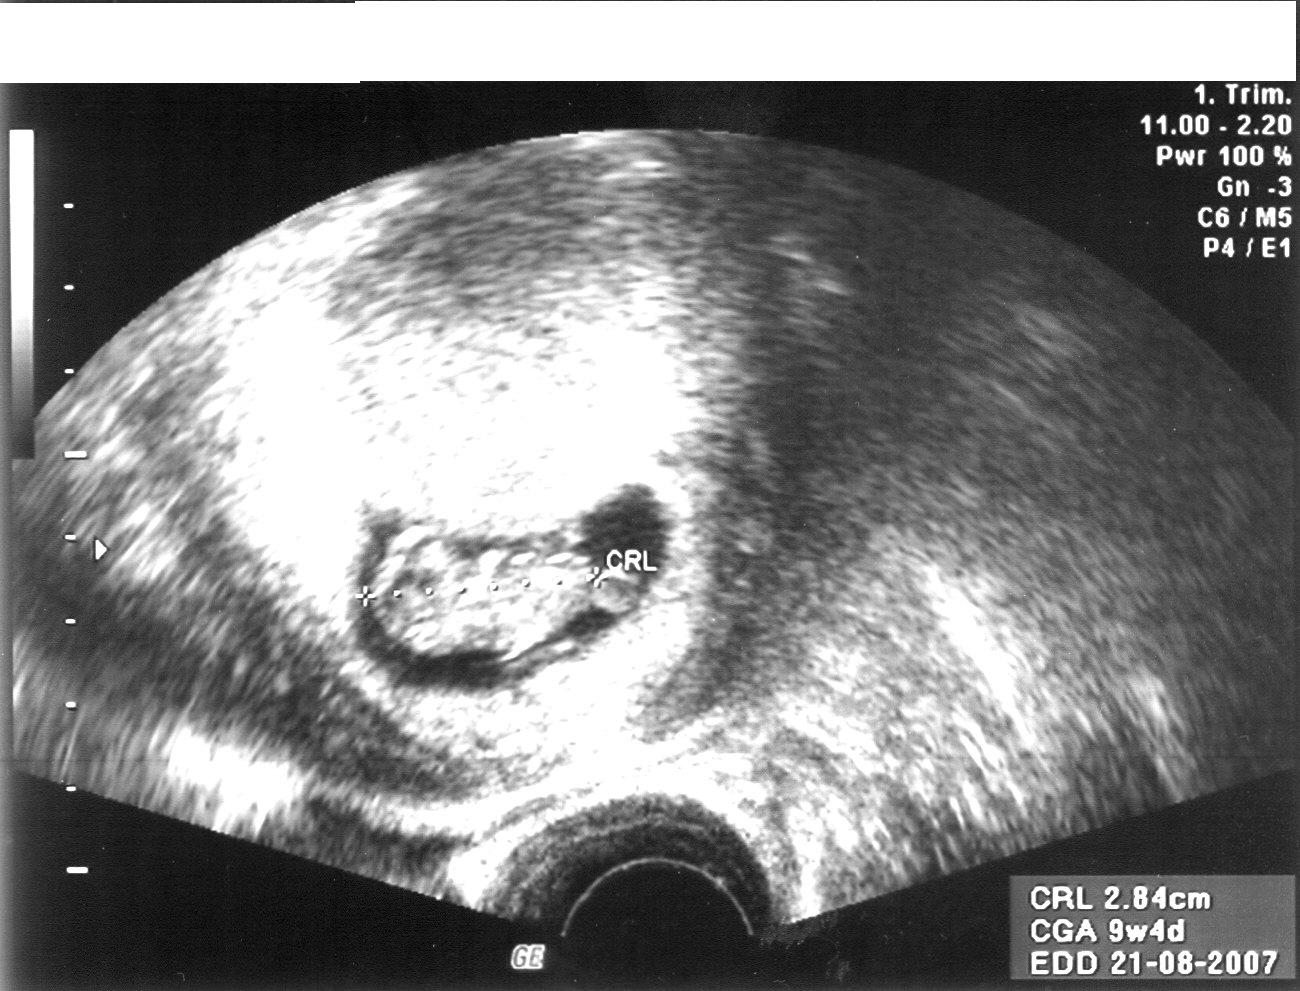

Hier mal schnell ein Sandy-Würmchen-Bild,melde mich später ausführlicher,muß noch meine Proluton abholen....

Steffi26 hat geschrieben:Saaandy:.......es hat geklappt![]()

!!! Oh, wie süss, 2,84 cm (hab mal wieder mein Geodreieck griffbereit

)!!!!

Putzig das Foto. Ich fand ja in dem Stadium sehen sie auf dem U-schallbild eher nach kleinem Vögelchen aus.